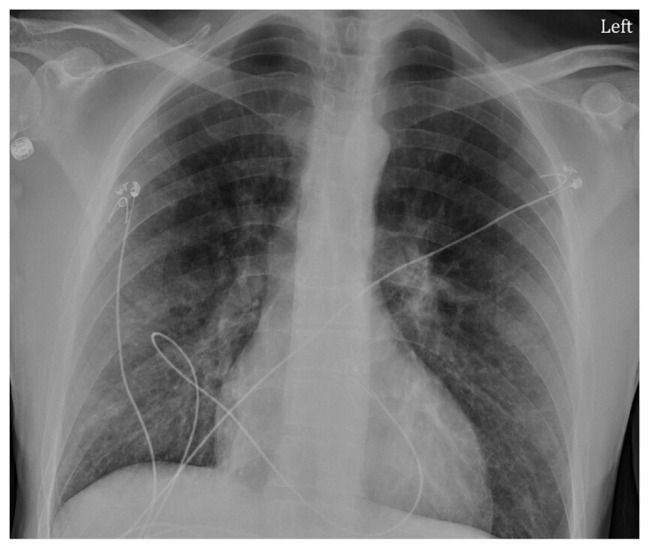

Abstract Image